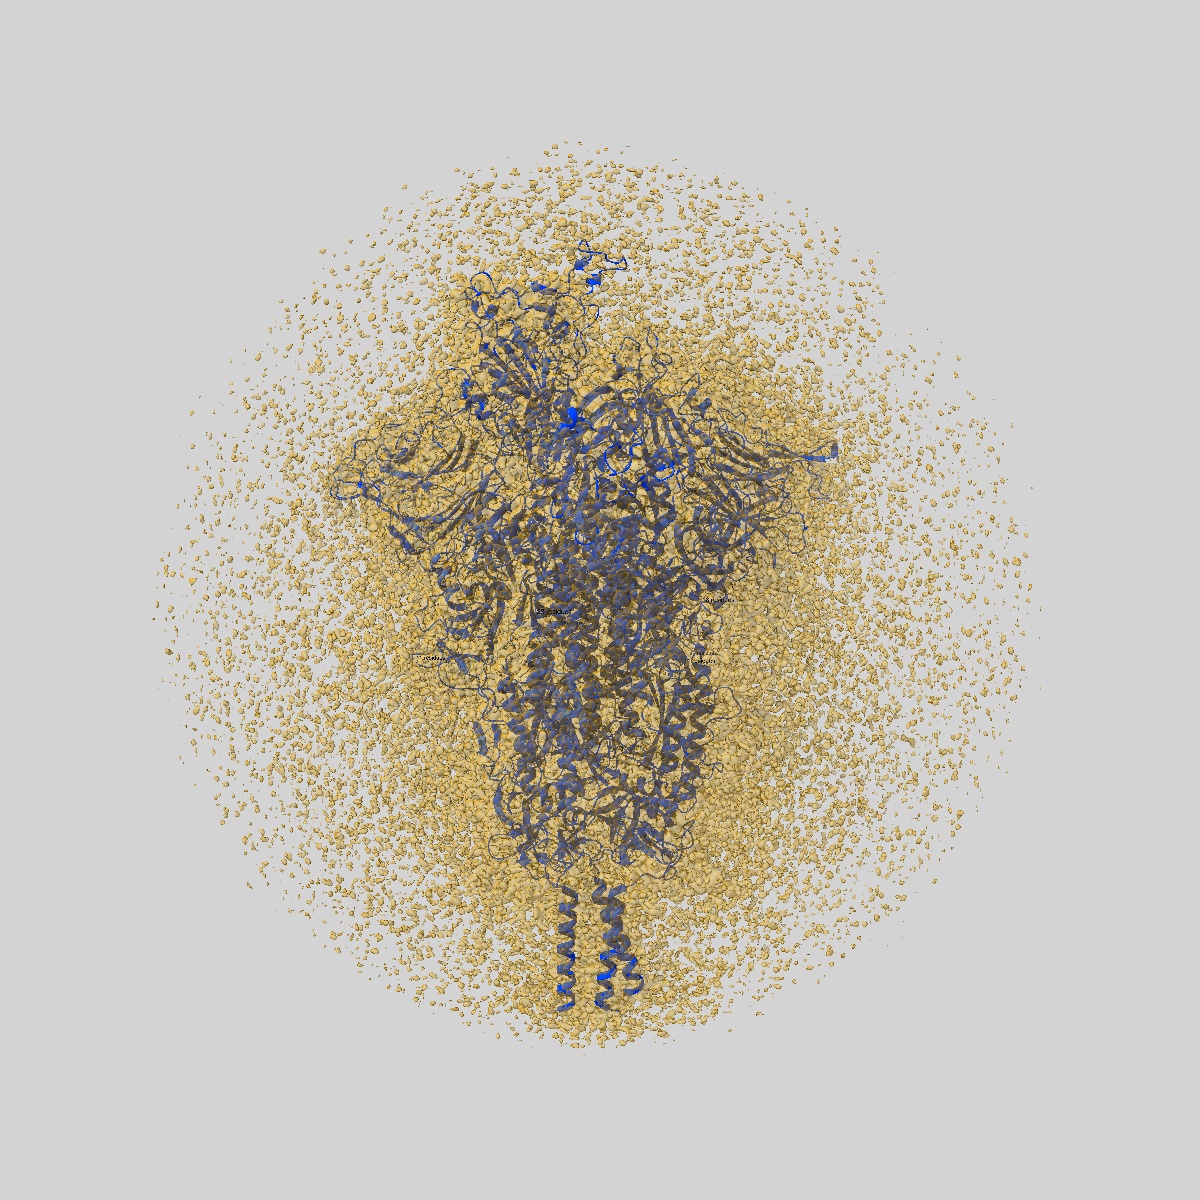

JN.1 SARS-COV-2 Spike 1-up conformation

Sample: S protein trimer

Fitted models: 9d8i

SARS-CoV-2 JN.1 and KP.2 spike characteristics and neutralization of JN.1-derived sublineages and T cell responses from mice immunized with monovalent JN.1- and KP.2-adapted BNT162b2 COVID-19 vaccines